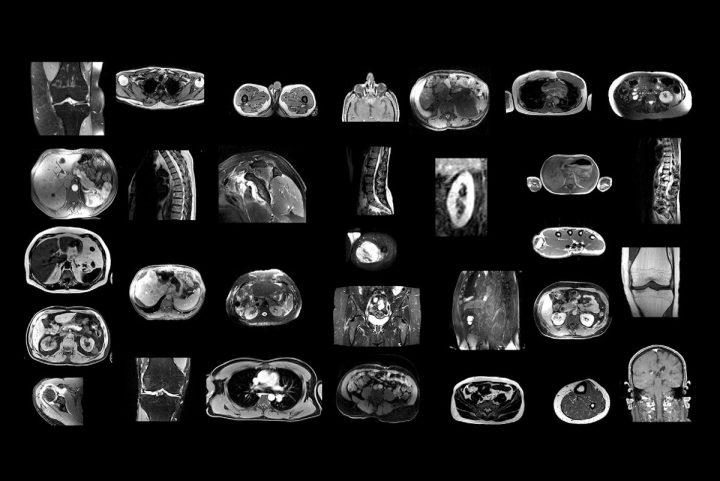

New AI model successfully segments anatomic structures in MR images February 18, 2025 By admin A Swiss research team has developed and tested an AI model that automatically segments anatomic structures on MR images independent of sequence.